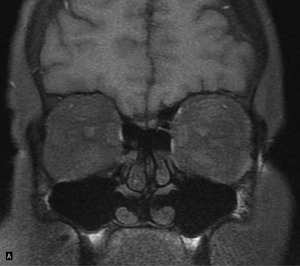

Rycina 1. Obraz T1-zależny bez saturacji tłuszczu w projekcji czołowej. Strzałki wskazują pogrubiałe mięśnie proste górne i dolne obu gałek ocznych. Badanie wykonane w pracowni MR Szpitala Praskiego, EUROMEDIC Polska

- pogrubienie mięśni prostych obu gałek ocznych, zwłaszcza prostych górnych i dolnych (ryc. 1)